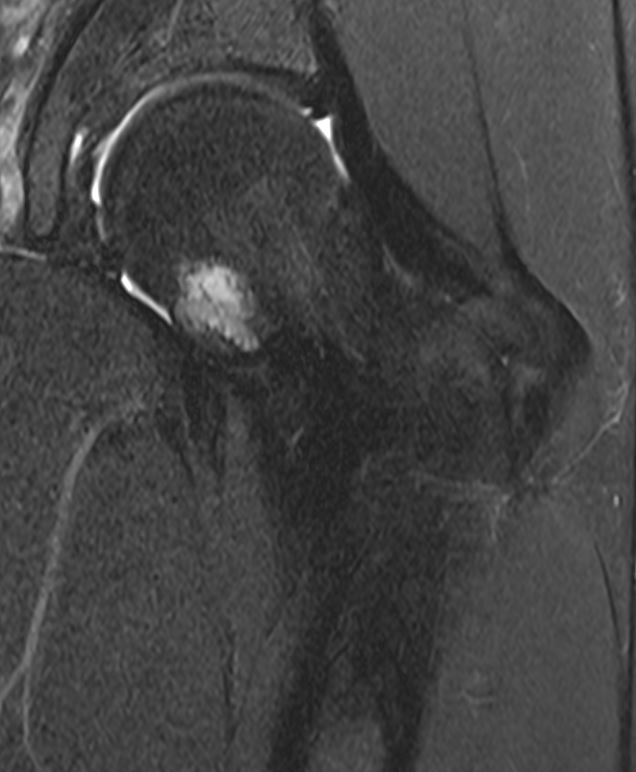

MRI

MR periosteal chondromaMR periosteal chondroma